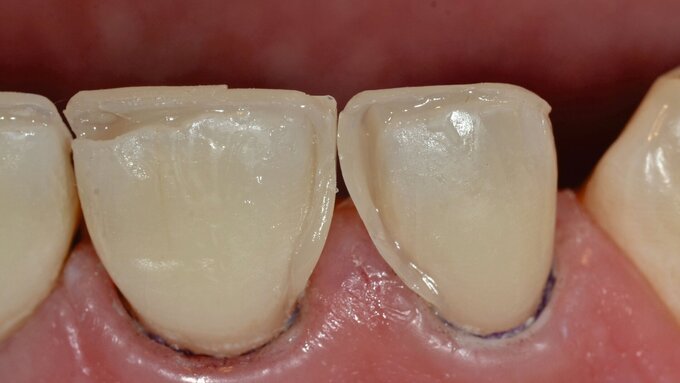

Im Anschluss wurde die Reparaturrestauration mit Komposit (Ceram X Spectra®/Dentsply Sirona) eingebracht (Abbildung 2i). Im Sinne des Restaurationsunterhalts wurden bei der Politur die Restaurationsränder der Gussmetall-Inlays an den Zähnen 24 und 25 finiert und zusammen mit der Kompositrestauration hochglanzpoliert (Abbildungen 2j und 2k).